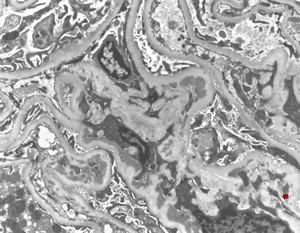

M,29y. | type II membranoproliferative glomerulonephritis (dense deposit disease)